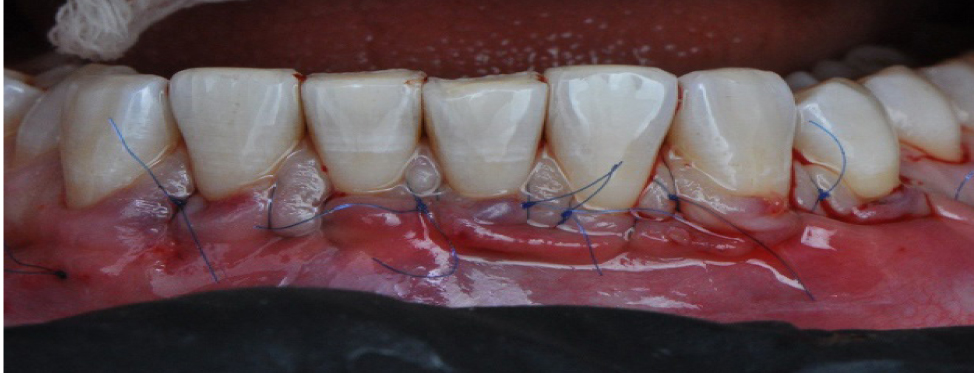

Произведен анализ 20 клинических случаев закрытия рецессий десневого края зубов на верхней и нижней челюстях по классификации Miller I и II класса, подкласса А и Б и классификации Francesco Cairo – 1-го и 2-го типа с применением туннельной техники по Zuhr (рис. 1). Операции проводились в период с 2019 по 2020 год. Средний возраст пациентов составил 31 год. Гендерное соотношение составило – 12 (60 %) женщин и 8 (40 %) мужчин, при этом на верхней челюсти произведено 13 (65 %) операций, а на нижней – 7 (35 %). Наличие гиперестезии в области зубов с рецессиями десневого края и эстетического дефекта – основные жалобы, которые предъявляли пациенты. Значение ширины зоны кератинизированной прикрепленной десны было вариабельно во всех клинических случаях и в среднем составляло 3 мм (норма – 4–9 мм). Уровень индивидуальной гигиены у всех обследованных находился на высоком уровне (PI < 20 %). Послеоперационный период наблюдения составлял от 1 года до 3 лет. Оценка эффективности устранения рецессии производилась на контрольных осмотрах через 3 и 6 месяцев, 1, 2 и 3 года путем определения следующих параметров: глубина и ширина рецессий (определение расстояния от цементно-эмалевого соединения до наиболее апикальной границы обнаженной поверхности корня), ширина зоны кератинизированной прикрепленной десны (ЗКПД), наличие или отсутствие рецидива, текстура и цвет мягких тканей в области вмешательства (оценка с помощью визуального контроля).

Рис. 1. Рецессия в области фронтальной группы зубов верхней челюсти Miller 1, Cairo Rt 1

Вначале проводилась антисептическая обработка полости рта 0,05%-м раствором хлоргексидина биглюконата, аппликационная и инфильтрационная анестезии. Затем выполнялись разрезы в области десневой борозды (сулькулярные) через каждую зону рецессии микрохирургическим лезвием с сохранением кончиков десневых сосочков (рис. 2), отслаивание полнослойных лоскутов с помощью микрохирургического распатора. Далее производился забор свободного десневого трансплантата с неба с последующей его внеротовой деэпителизацией и наложением на зону забора параллельных и перекрестных горизонтальных обвивных швов (рис. 3). Позиционирование и фиксация трансплантата в принимающем ложе, ушивание раневой поверхности швами Аллена (рис. 4). Даны рекомендации по послеоперационному ведению: полоскания 0,05%-м раствором хлоргексидина биглюконата 2 раза в день в течение 2 недель, назначены противовоспалительные и обезболивающие лекарственные препараты (НПВС). Повторная явка через день. Швы снимались на 7–10-е сутки. Контрольные осмотры проводились через 3 и 6 месяцев, 1, 2 и 3 года соответственно, оценивалось состояние мягких тканей в области хирургического вмешательства и степень закрытия рецессий десневого края.

Рис. 2. Внутрибороздковые разрезы микрохирургическим лезвием